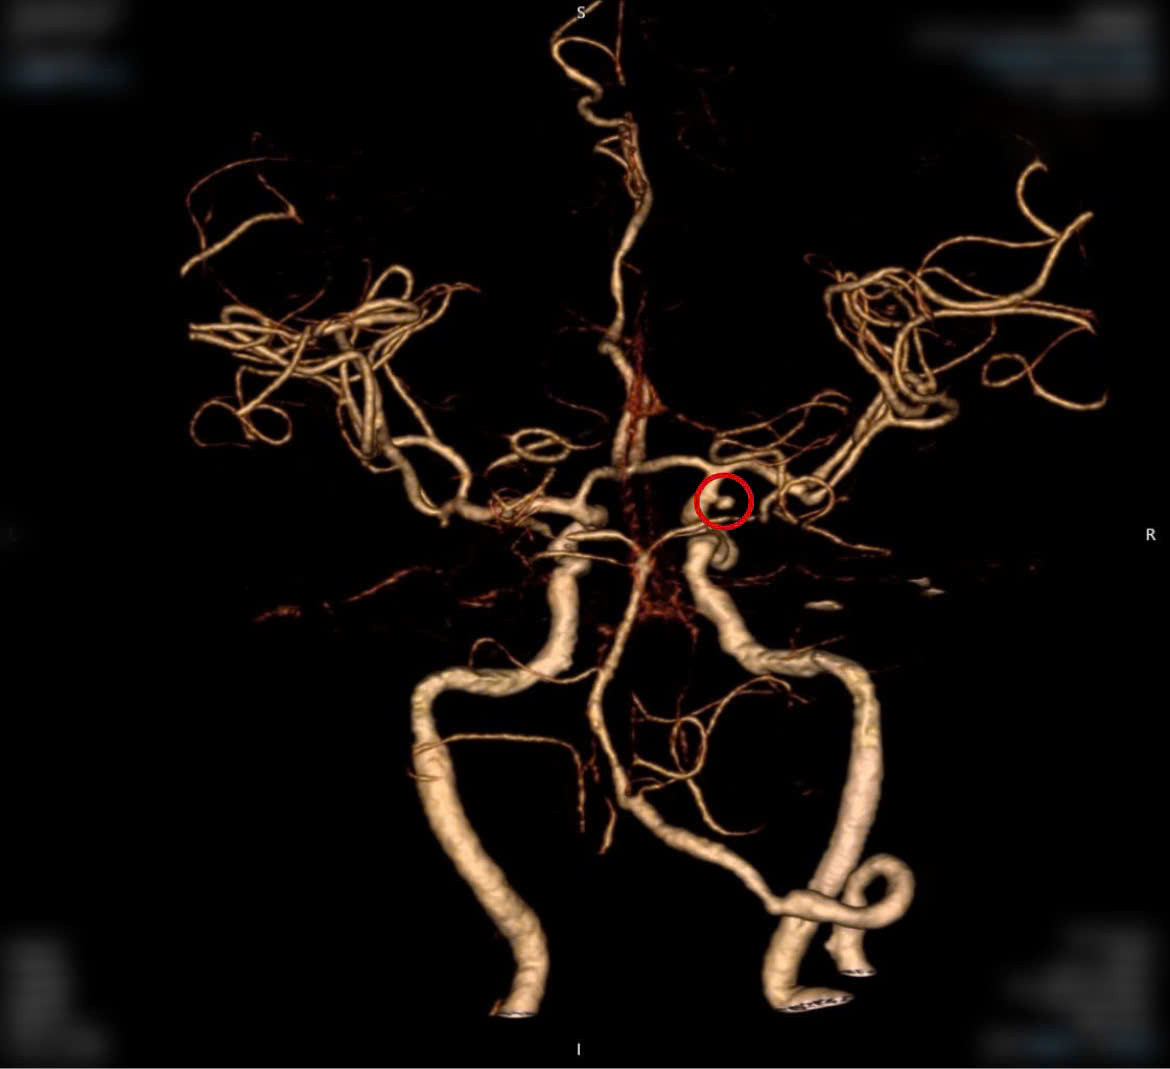

| Hình ảnh mạch máu của bệnh nhân trên phim CTA- tình cờ phát hiện 1 túi phình động mạch (vị trí khoanh tròn đỏ) |